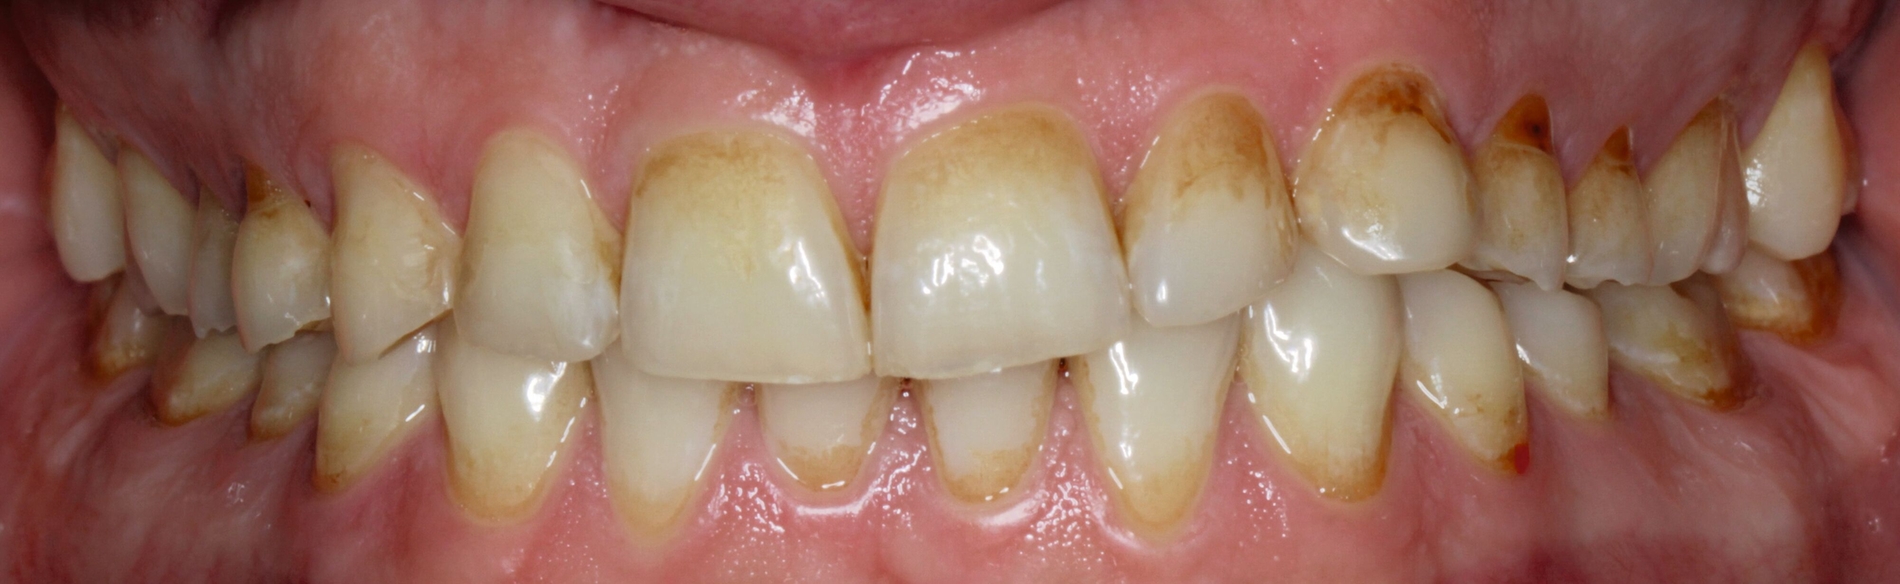

Klinisch präsentierte sich ein vollbezahntes Gebiss ohne Weisheitszähne mit Defekten an der Zahnstruktur teilweise bis ins Dentin. Es waren deutliche Erosionsspuren zu erkennen, die auf die säurehaltige Ernährung im Kurzzeitintervall zurückgeführt wurden. Der BEWE-Index war mit dem Wert 13 auffällig und kategorisierte den Schaden als ausgeprägte Erosionen. Die Zähne 14, 13 und 24 wiesen nicht-kariöse zervikale Defekte auf, diese treten häufig im Zusammenhang mit Bruxismus auf [Pecie et al., 2011]. Das CMD-Screening der Deutschen Gesellschaft für Funktionsdiagnostik und -therapie (DGFDT) [DGFDT, 2024] war unauffällig, da der Patient über keinerlei Schmerzen oder Beschwerden bei Kieferbewegungen klagte. Die manuelle Strukturanalyse (MSA) nach Bumann [Fasold und Kordaß, 2012] ergab bei diesem Patienten ein myofaziales Schmerzsyndrom. Im Prämolarenbereich imponierten Zahnhartsubstanzdefekte, die Hinweise auf starkes und häufiges Zähnepressen geben. Den Patienten selbst störten seine kälteempfindlichen Zähne sowie die Gesamtästhetik aufgrund des massiven Substanzverlustes.

Der Patient konnte vollständig saniert werden und kam mit der neu eingestellten Bisshöhe sehr gut zurecht. Während der Behandlung wurden Ernährungshinweise gegeben, um die langfristige Haltbarkeit der Restauration zu gewährleisten. Eine besondere Herausforderung stellten in diesem Fall der angestrebte Ausgleich der verlorenen vertikalen Höhe und die Bestimmung der Myozentrikposition dar.